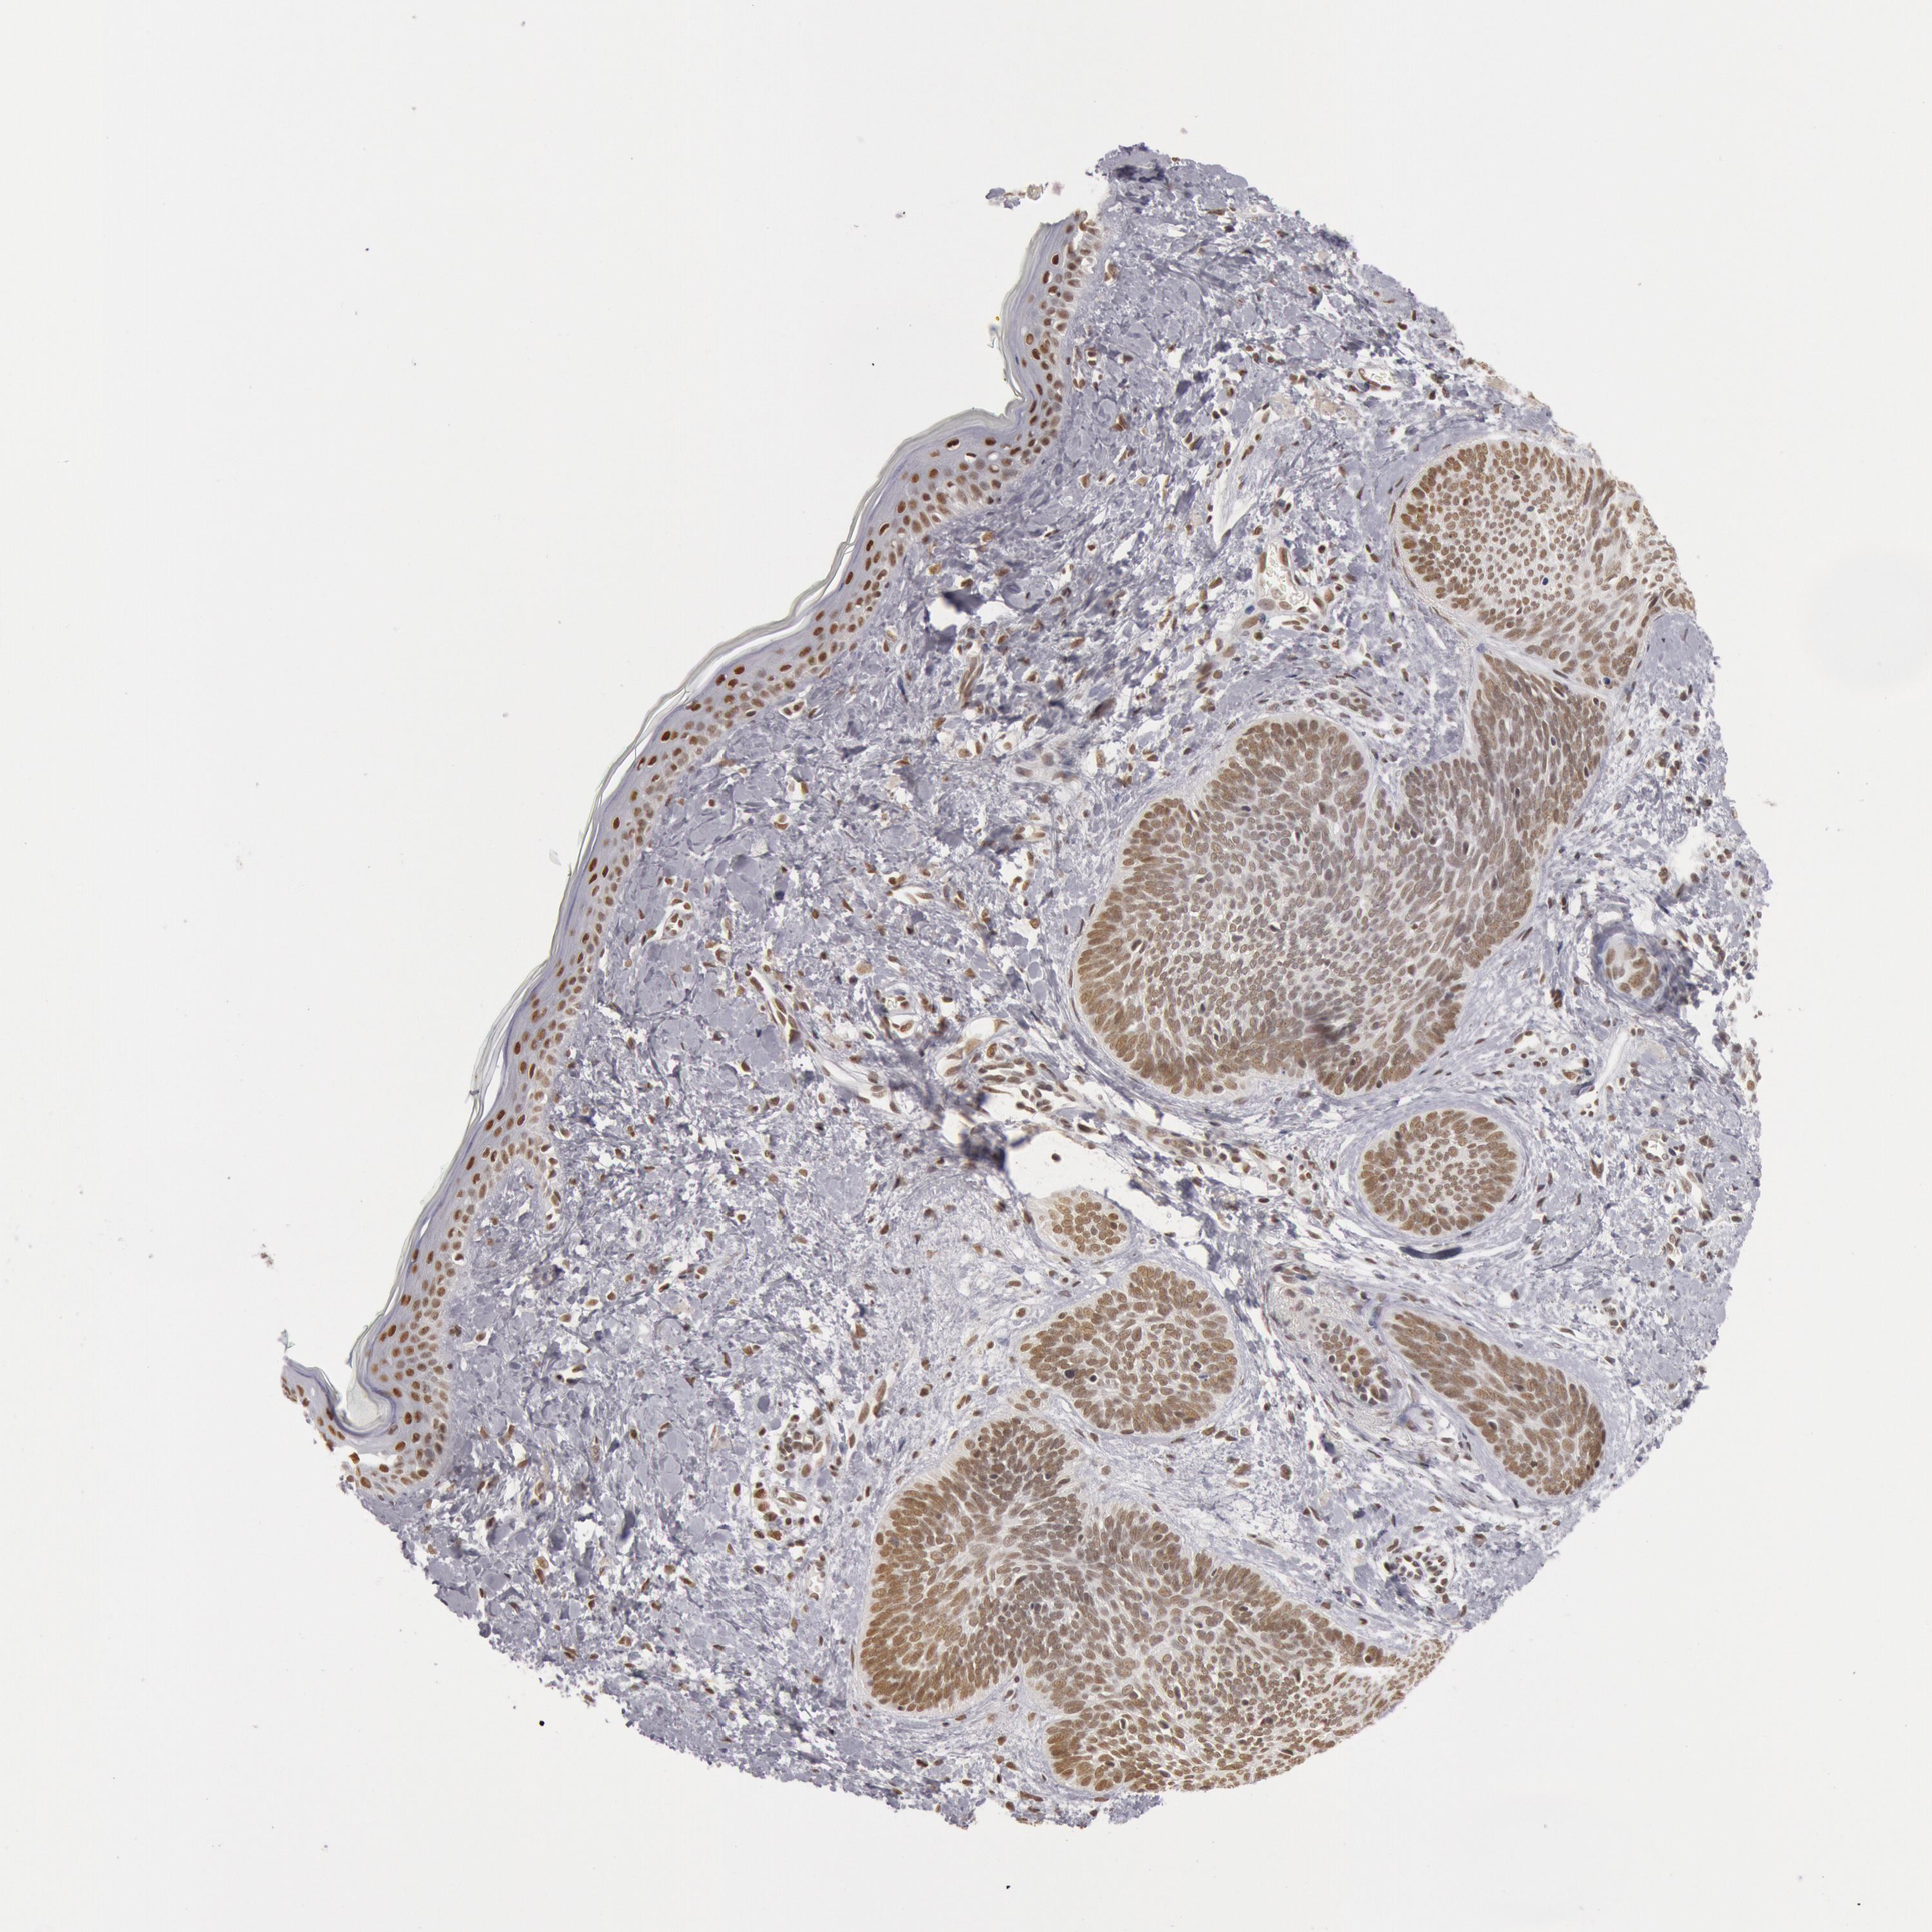

SKIN CANCER - Protein expressioni

A mouse-over function shows sample information and annotation data. Click on an image to view it in a full screen mode. Samples can be filtered based on level of antibody staining by selecting one or several of the following categories: high, medium, low and not detected. The assay and annotation is described here.

Antibody stainingi

Antibody staining in the annotated cell types in the current human tissue is reported as not detected, low, medium, or high, based on conventional immunohistochemistry profiling in selected tissues. This score is based on the combination of the staining intensity and fraction of stained cells.

Each image is clickable and will lead to virtual microscopy that enables deeper exploration of all samples and also displays staining intensity scores, fraction scores and subcellular localization as well as patient and tissue information for each sample.

Antibody HPA001221

Antibody HPA001222

Staining

High

Medium

Low

Not detected

Intensity

Strong

Moderate

Weak

Negative

Quantity

>75%

75%-25%

<25%

None

Location

Nuclear

Cytoplasmic/membranous

Cytoplasmic/membranous,nuclear

Squamous cell carcinoma, NOS

Basal cell carcinoma